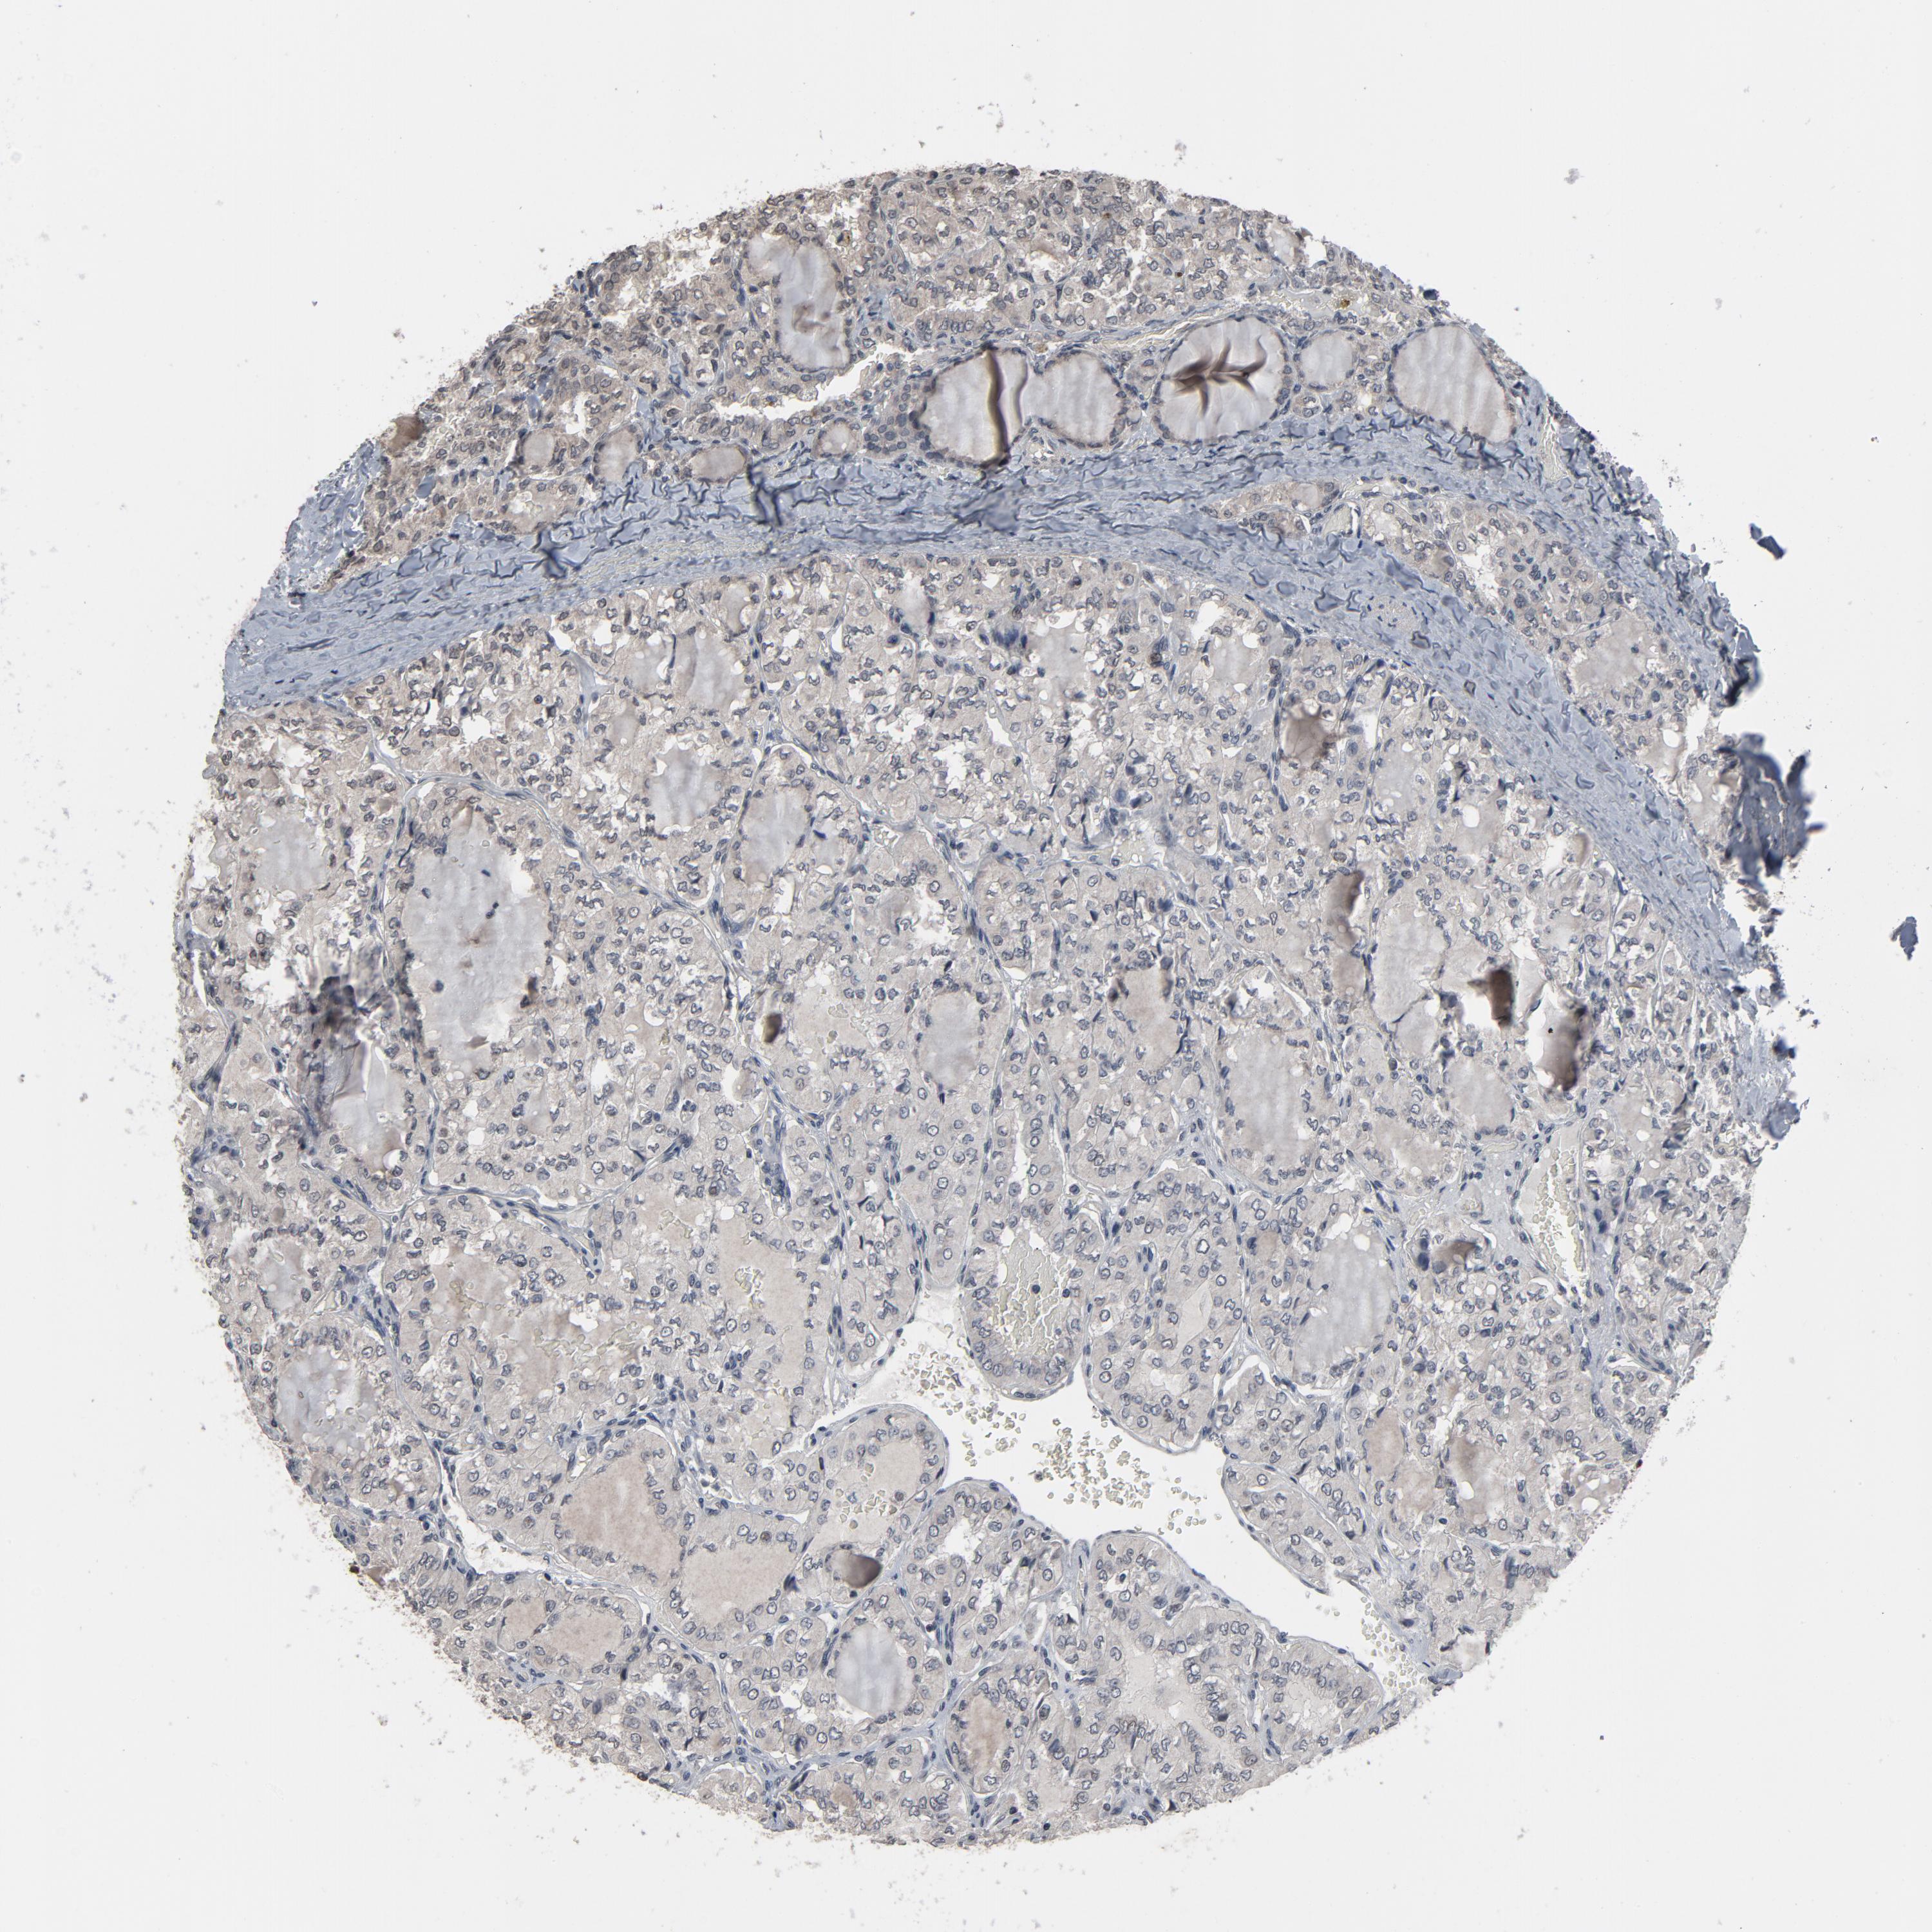

THYROID CANCER - Protein expressioni

A mouse-over function shows sample information and annotation data. Click on an image to view it in a full screen mode. Samples can be filtered based on level of antibody staining by selecting one or several of the following categories: high, medium, low and not detected. The assay and annotation is described here.

Note that samples used for immunohistochemistry by the Human Protein Atlas do not correspond to samples in the TCGA dataset.

Antibody stainingi

Antibody staining in the annotated cell types in the current human tissue is reported as not detected, low, medium, or high, based on conventional immunohistochemistry profiling in selected tissues. This score is based on the combination of the staining intensity and fraction of stained cells.

Each image is clickable and will lead to virtual microscopy that enables deeper exploration of all samples and also displays staining intensity scores, fraction scores and subcellular localization as well as patient and tissue information for each sample.

Antibody HPA043809

Antibody HPA049817

Antibody CAB003710

Staining

High

Medium

Low

Not detected

Intensity

Strong

Moderate

Weak

Negative

Quantity

>75%

75%-25%

<25%

None

Location

Nuclear

Cytoplasmic/membranous

Cytoplasmic/membranous,nuclear

Follicular adenoma carcinoma, NOS

Papillary adenocarcinoma, NOS

Carcinoma, NOS